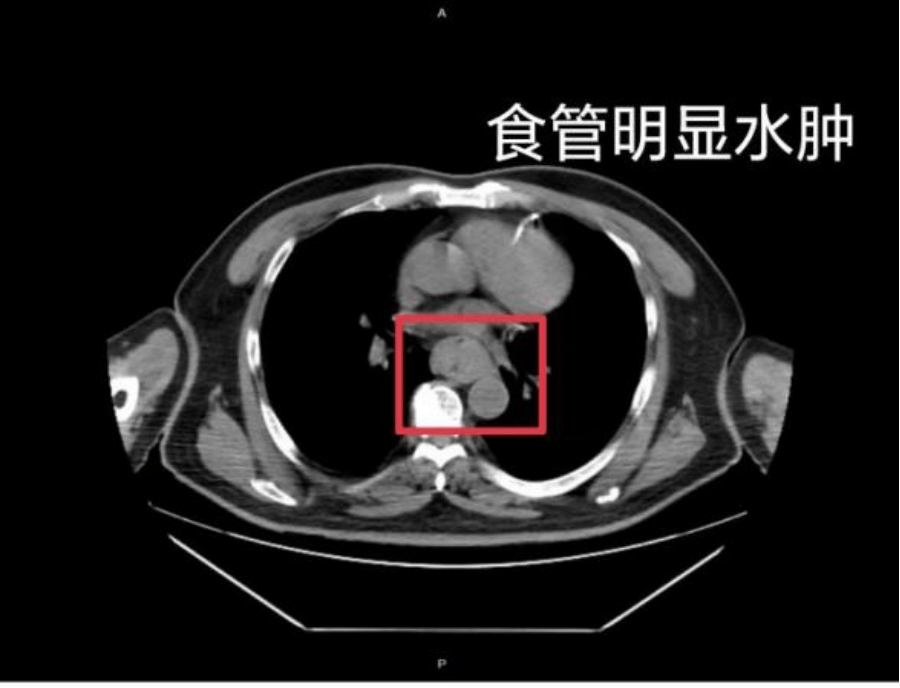

这样的情况并非个例,同样在近日,福州一位网友分享了自己因吃了一碗很烫的福鼎肉片导致呕血,并查出食管水肿的经历虚拟币挖矿整治措施。

据网友回忆,“自己去厕所尝试呕吐时,直接呕出了血,一大口鲜血从嘴里喷出,总共吐了两次虚拟币挖矿整治措施。”CT 结果显示,他的食管全部出现水肿损伤。